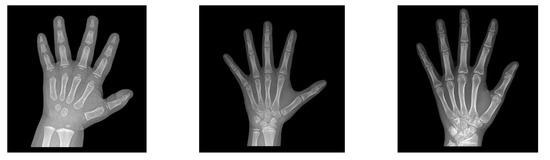

In order to clearly illustrate the input data of this paper, we sample three pictures from each stage of the data in Table 1, as shown in Figure 1, from left to right are toddlers (S1), puberty (S2) and post-puberty (S3) stages.

Figure 1. Three-stage metacarpal X-ray images.